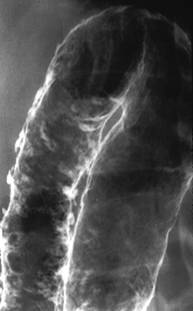

Examenul radiologic cu dublu contrast apreciaza distensibilitatea colonului. Initial se evidentiaza aspectul neregulat, fin granular al mucoasei, scaderea distensibilitatii colonului si dehaustrarea. Ulterior apar ulceratiile ce dau pe imaginea de profil aspectul de spiculi marginali si imagini de aditie, iar pe cea de fata pete opace suspendate. In stadiile avansate apar ulceratiile "in buton de camasa". Examenul radiologic cu substana de contrast este contraindicat in RCUH severa/fulminanta, avand risc de precipitare a megacolonului toxic.

Colita ulcerativa -puseu de activitate- Colita ulcerativa cronica-dehaustrarea

ulceratii si inflamatia extensiva sigmoidului

a mucoasei